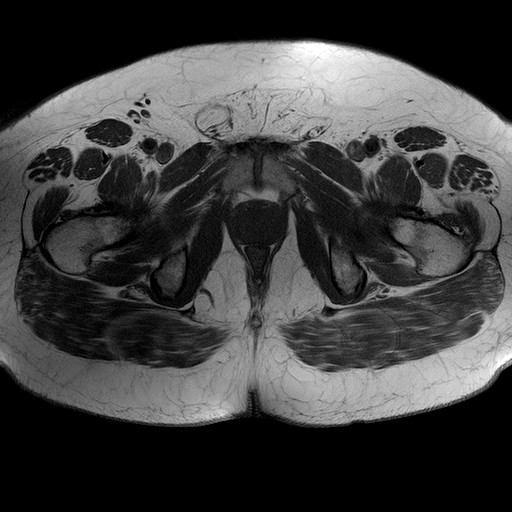

Esami: RMN BACINO

T1W_TSE

Evidenti e simmetriche alterazioni osteofitosiche in regione coxo femorale con riduzione delle rime articolari. Degenerazione completa del cercine glenoideo. Non attuali segni di versamento articolare. Non segni di edema osseo che escludono attuale algodistrofia od osteonecrosi. Lieve e simmetrica riduzione del trofismo della muscolatura glutea.